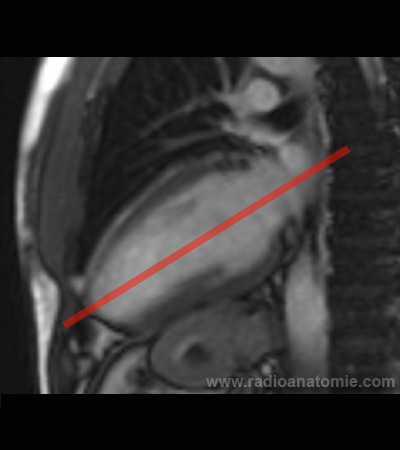

Radioanatomie et plans de coupe en IRM cardiaque

Plan chambre de chasse du ventricule gauche (LVOT)